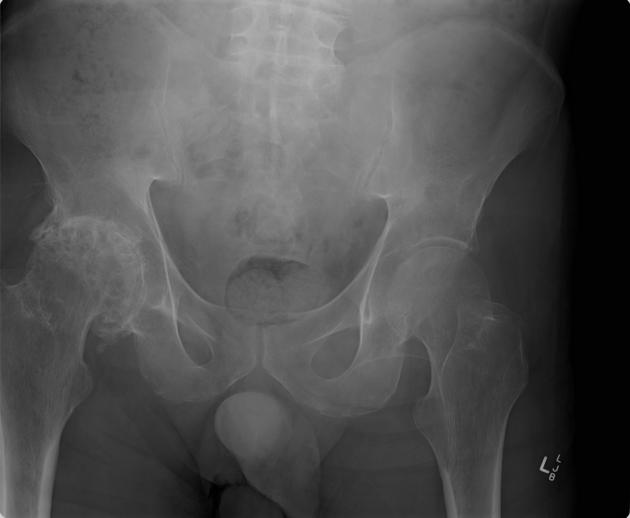

The crux of my first project in this lab involved taking patients from the UK Biobank who had been diagnosed with hip osteoarthritis (OA) and attempting to train a classifier using machine learning (ML) on X-rays of these patients' hips. Hip OA is typically diagnosed by looking at X-rays of the hip, specifically looking at the hip-joint space between the hip and the pelvis as well as other diagnostic markers more clearly described here. In the image below, the hip on the left side of the picture has OA while the right hip is normal.